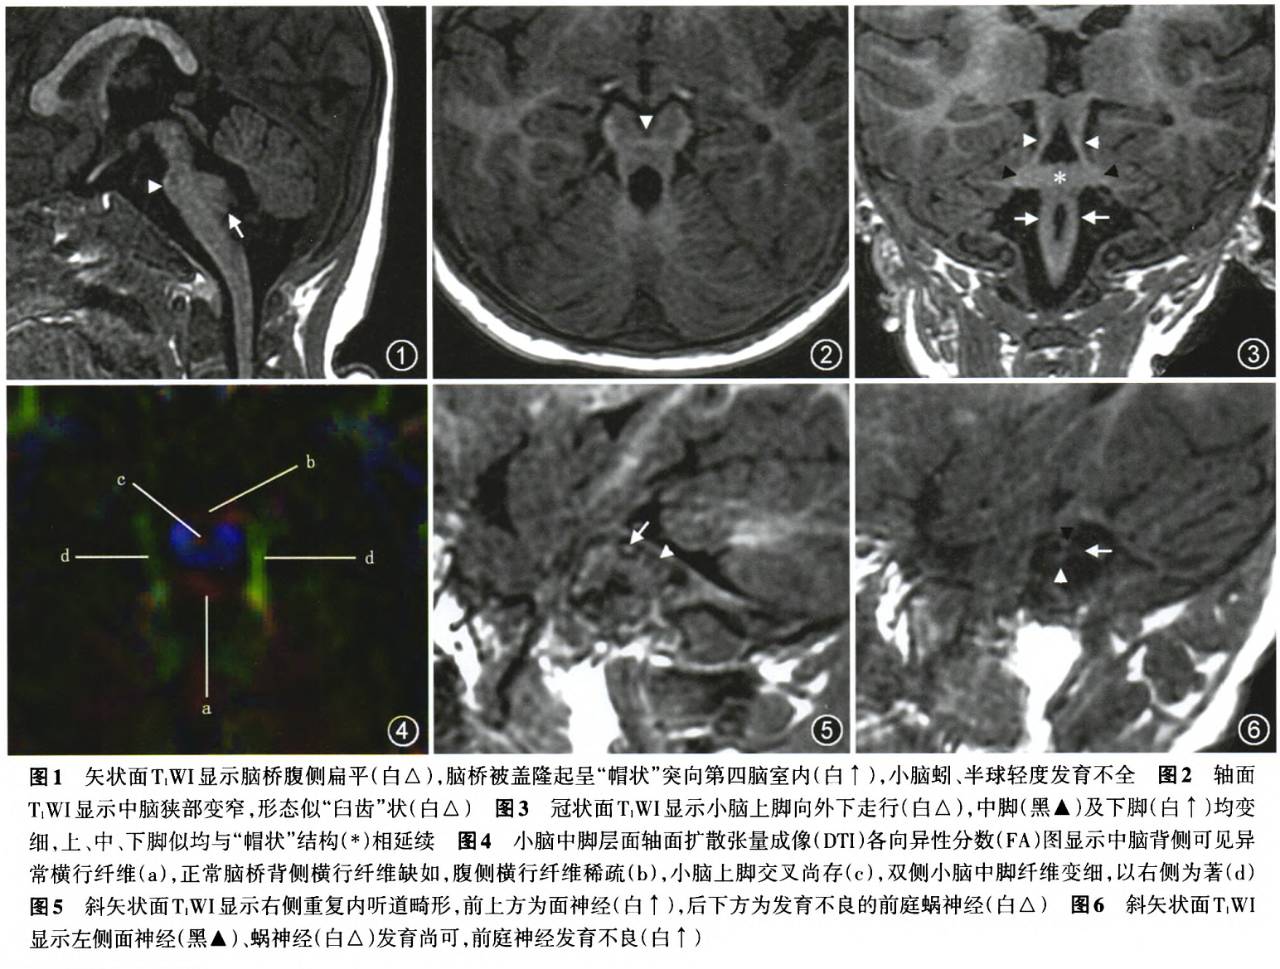

MRI检查:颅脑矢状面T1WI显示脑桥腹侧扁平,脑桥被盖隆起呈“帽状”突向第四脑室内,小脑蚓、半球轻度发育不全(图1)。轴面T1WI显示中脑狭部变窄,形态似“臼齿”状(图2),冠状面T1WI显示小脑上脚向外下走行,中脚及下脚均发育不良,上、中、下脚似均与“帽状”结构相延续(图3)。小脑中脚层面轴面扩散张量成像(DTI)的各向异性分数(FA)图显示中脑背侧可见异常横行纤维,构成第四脑室的前缘。正常脑桥背侧横行纤维缺如,腹侧横行纤维稀疏,小脑上脚交叉尚存,双侧小脑中脚纤维变细,以右侧为著(图4)。右侧重复内听道畸形,左侧内听道变窄,双侧前庭蜗神经发育不良,以右侧为著(图5,6)。

本病最具特征性的影像表现为脑桥腹侧扁平,被盖呈“帽状”隆起,突向第四脑室内。DTI扫描显示被盖“帽状”结构由异常横行纤维构成,而正常脑桥背侧横行纤维缺如,腹侧横行纤维稀疏,提示本病可能存在脑桥横行纤维的异位。在常规冠状面T1WI上,“帽状”结构似与小脑上脚、中脚及下脚相延续,但纤维示踪图显示这些横行纤维与周围结构均无连接,这可能是由于DTI技术的限制所致”(当FA值或纤维束的角度低于特定的阈值时,纤维示踪终止),随着DTI技术的改进可更好地显示这些纤维束的走行,对于揭示本病的发生能起到重要作用。

前庭蜗神经发育不良为本病的另一特征。本例患儿显示双侧内听道变窄,前庭蜗神经发育不良,以右侧为著。因此,对所有感音神经性听力丧失的患儿需要注意观察脑桥的形态,以避免漏诊。